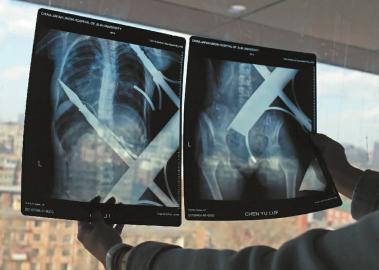

X光片顯示一根鋼筋將小女孩的右側(cè)肩膀刺穿,另外一根則從后背腰部以上靠近脊椎的地方穿入 白石 攝

在急診室的病床上,李紅旭看到了小雨?!八龗熘跗浚庾R(shí)比較清醒?!边M(jìn)一步觀察,李紅旭一時(shí)說(shuō)不出話(huà)來(lái)———一根鋼筋穿透小雨右側(cè)肩膀,另一根則從后背腰部以上靠近脊椎的地方穿入,從小雨左肩部分穿了出來(lái)。兩根鋼筋由兩根角鐵連接,距離事發(fā),小雨背著這片鐵柵欄已經(jīng)近7個(gè)小時(shí)了。